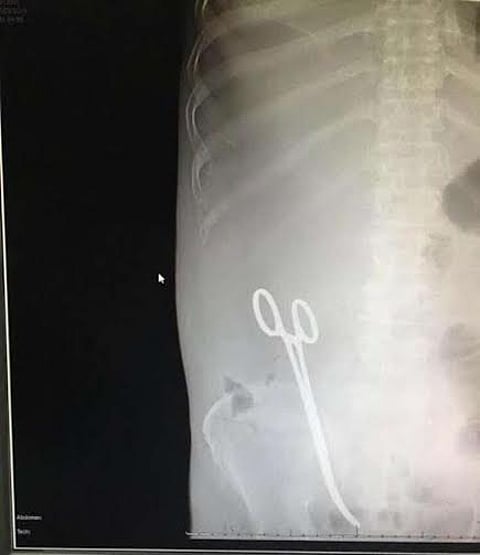

أكدت "صحة حائل" في بيان لها، حول حادثة نسيان مقص داخل بطن مريض أثناء عملية جراحية، أن الحادثة جسيمة، وتم تسجيلها عبر برنامج الأحداث الطبية الجسيمة في وزارة الصحة.

وأضاف البيان الذي صدر من عارف بن غازي الشمري، المتحدث الرسمي بصحة حائل، بأن المدير العام للشؤون الصحية بمنطقة حائل أمر بالتحقيق في أسباب حدوث ذلك وملابساته، ومحاسبة المتسبب فيه، وأنه تم منع جميع من شارك بهذا الخطأ من الممارسين الصحيين المتعاقدين من السفر حتى انتهاء التحقيق.

وقدمت "صحة حائل" اعتذارها لما حدث للمريض، مؤكدة للجميع حرصها التام على صحة وسلامة المرضى.